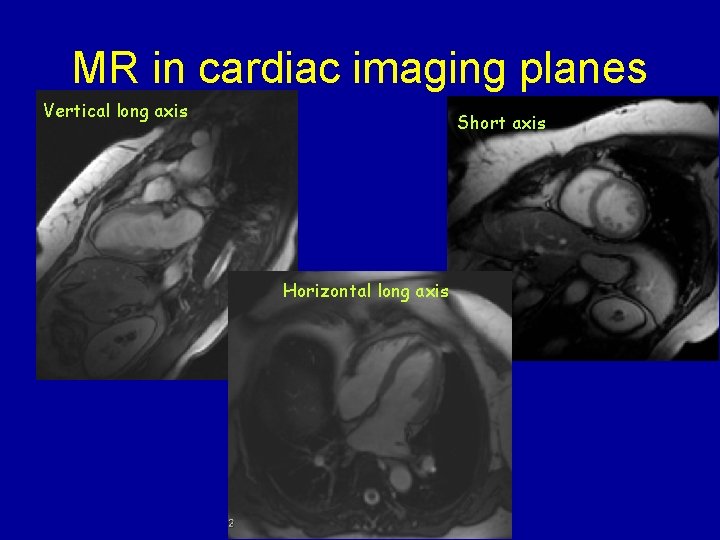

Imaging planes for cardiac MR/Echo Vertical long axis Horizontal long axis Short axis

MR in cardiac imaging planes Vertical long axis Short axis Horizontal long axis